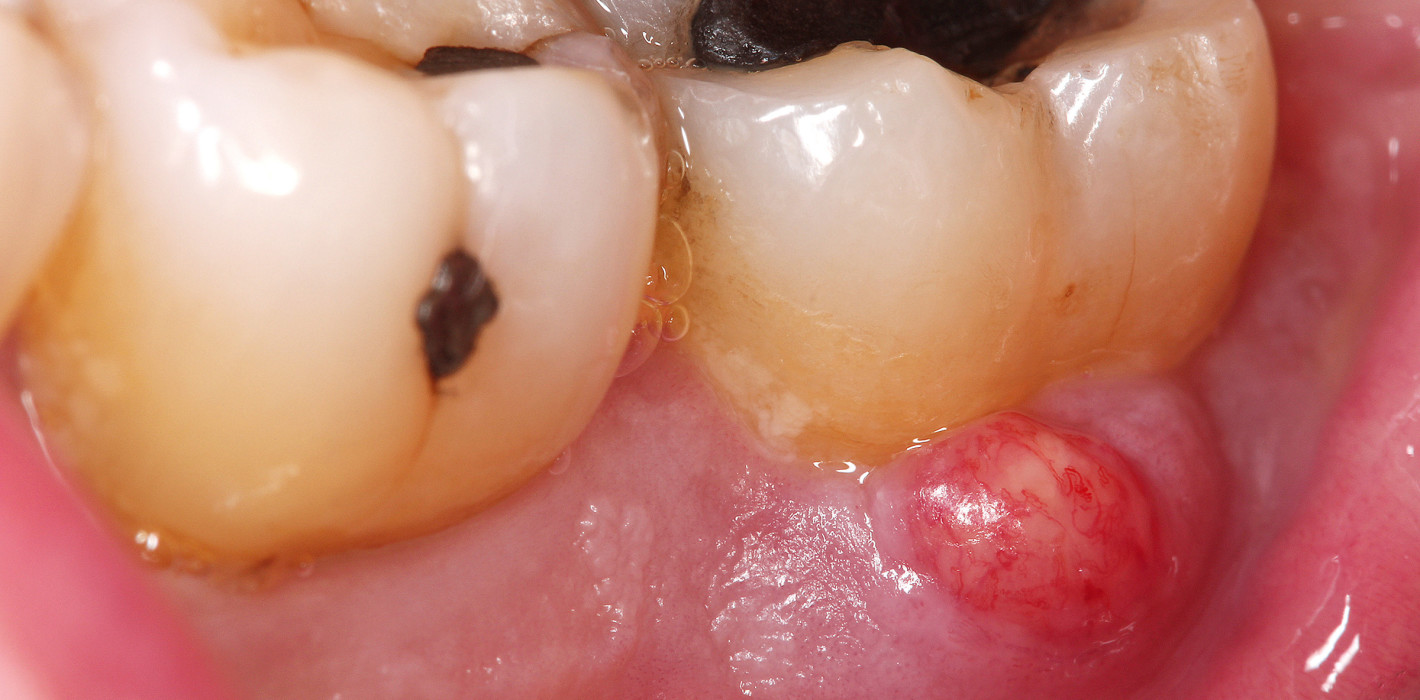

Source: godpollsqvu.pages.dev Aphte geht nicht weg, Fistel? (Gesundheit und Medizin, Zahnarzt, Mundhygiene) , Verursacht eine Fistel am Zahnfleisch Schmerzen? Eine Fistel äußert sich meist als ein kleines weißes Bläschen mit einem roten Hof darum herum in der unmittelbaren Nähe des betroffenen Zahns Anschliessend bildet sich ober- beziehungsweise unterhalb des betroffenen Zahns ein Bläschen am Zahnfleisch, das sich im weiteren Verlauf mit Eiter füllt.

Source: farivenawiy.pages.dev ¿Qué es una fístula dental y cómo se trata? Chapin TV , Angestauter Eiter entleert sich selbsttätig über die Öffnung, sobald der Druck im Grund zu hoch wird. Verursacht eine Fistel am Zahnfleisch Schmerzen? Eine Fistel äußert sich meist als ein kleines weißes Bläschen mit einem roten Hof darum herum in der unmittelbaren Nähe des betroffenen Zahns

Source: nishuangnhk.pages.dev Was ist eine Zahnfistel (Fistel im Mund)? netDoktor.de , Anschliessend bildet sich ober- beziehungsweise unterhalb des betroffenen Zahns ein Bläschen am Zahnfleisch, das sich im weiteren Verlauf mit Eiter füllt. Angestauter Eiter entleert sich selbsttätig über die Öffnung, sobald der Druck im Grund zu hoch wird.

Aphte geht nicht weg, Fistel? (Gesundheit und Medizin, Zahnarzt, Mundhygiene) In einigen Fällen klingen die Schmerzen ab, wenn der Eiter abfließt, kehren jedoch bei erneuter Ansammlung zurück Eine Behandlung mit Medikamenten lindert die Schmerzen, führt aber keine. Schmerzen: Vor allem bei Druck auf den betroffenen Zahn oder das Zahnfleisch können starke Schmerzen auftreten